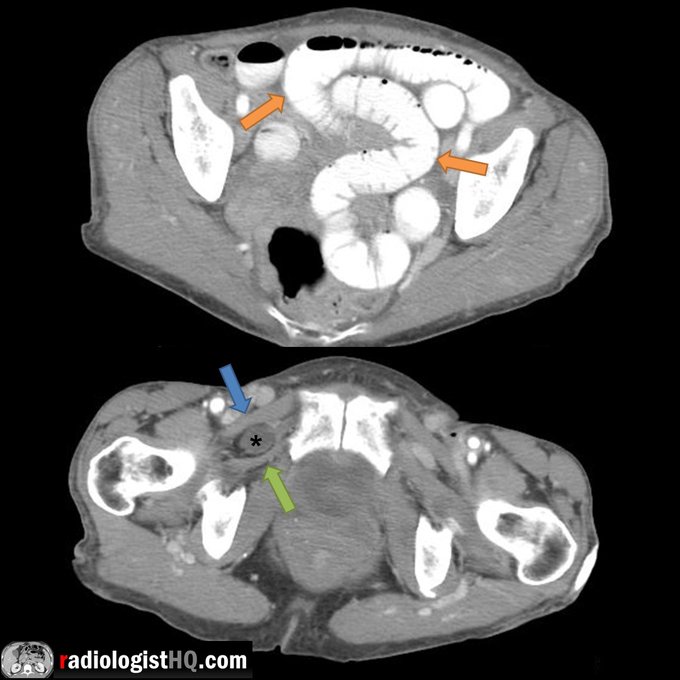

CT of small bowel obstruction caused by obturator hernia. Dilated small bowel loops (orange) with obstructed loop in obturator hernia (*) betwixt the pectineus (blue) &obturator externus (green arrow) muscles.

#FOAMrad #FOAMed #radiology #radres #medstudent #radiologisthq